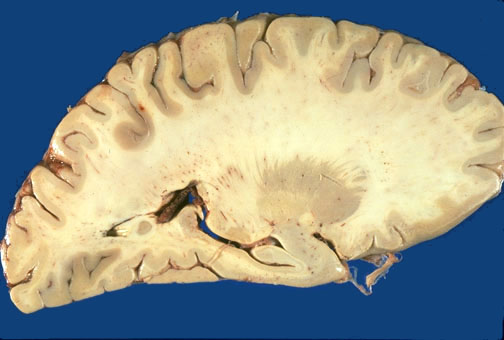

| Identify the following regions of the brain on sagittal section through the hippocampus in the image above: Putamen - Globus Pallidus - Anterior Commissure - Lateral Geniculate Nucleus - Hippocampus - Amygdala - Choroid Plexus of Lateral Ventricle - Pulvinar - Corona Radiata - |